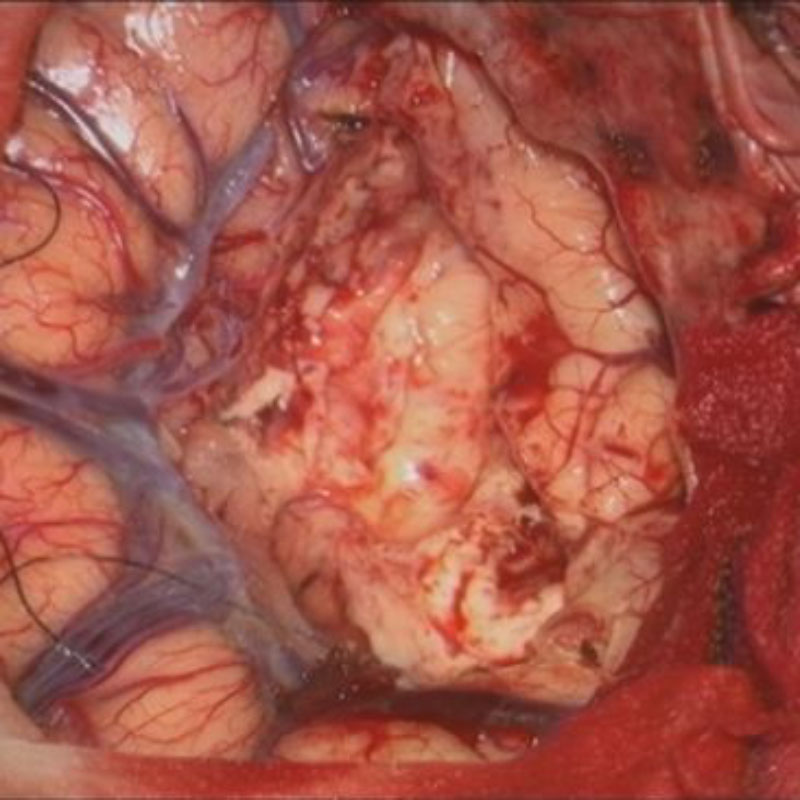

No.’24_47 摘出 前

No.’24_47  摘出 中

No.’24_47 摘出 後